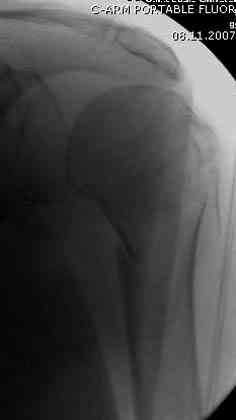

Наш недавний случай перкутанной фиксации "методом

Сиэтла" спицами 2.8 мм с резьбой на конце.

Под проводниковой анестезией произвел попытку закрытой репозиции на 10-е сутки, вроде бы неплохо получилось.

Извиняюсь за качества снимков, обычный больной в 300 фунтов, портативным ренген аппаратом не пробить.